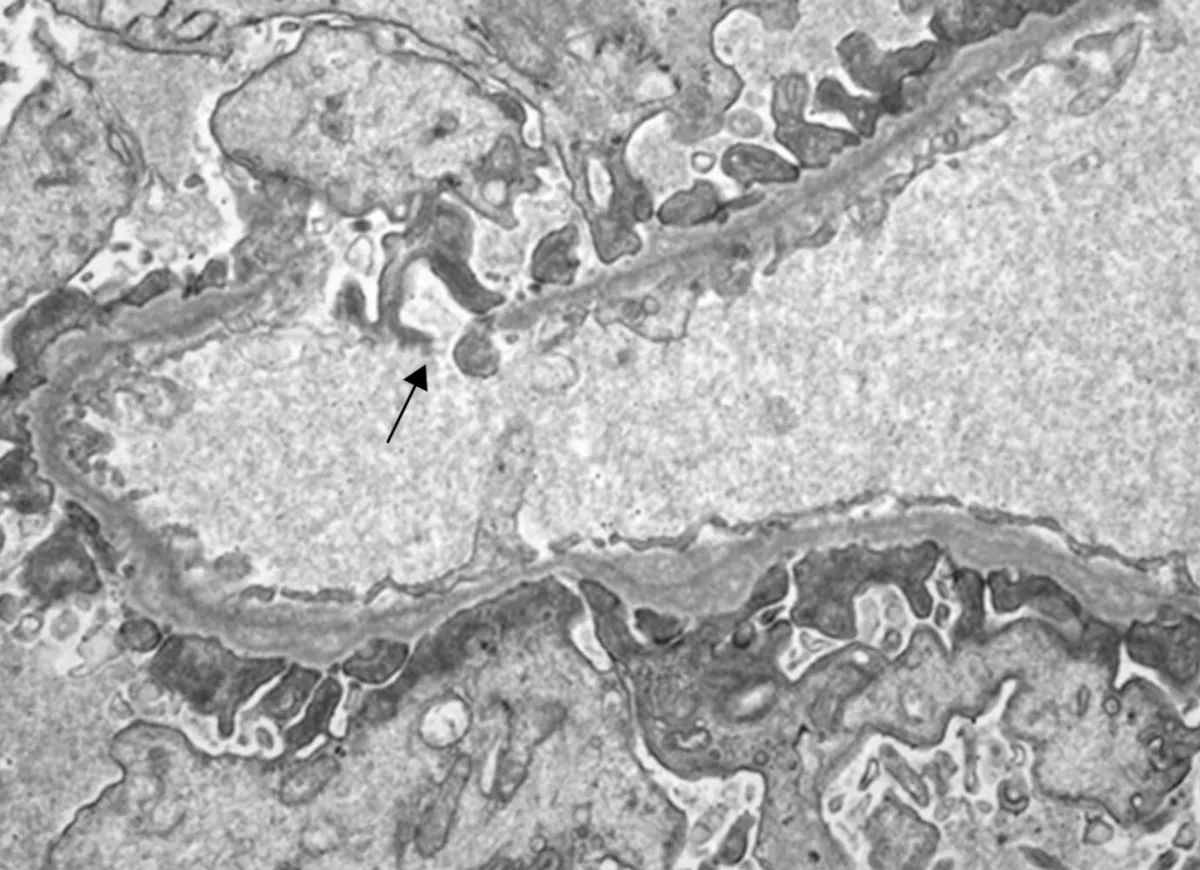

Variabilidade Clínica e Riscos de Progressão

Portadores de mutações em heterozigose apresentam um espectro clínico que varia de assintomático a quadros de hematúria isolada ou desenvolvimento proteinúria, hipertensão e eventual disfunção renal. A progressão para falência renal ocorre em uma minoria dos casos, sendo o risco estimado de DRC G5 aos 60 anos inferior a 3%. Estudos populacionais indicam prevalência elevada dessas variantes em indivíduos sem sinais clínicos evidentes, sugerindo que muitos casos sejam subdiagnosticados.